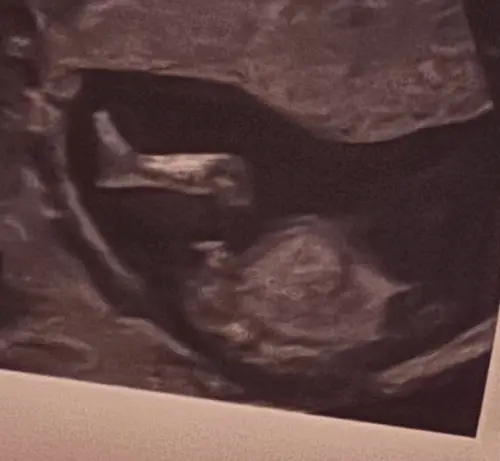

Gokje wagen, meisje of jongen? ( Nub-theorie)

Wat denken jullie? Jongen of meisje

BamiSalami

Meisje 馃槉